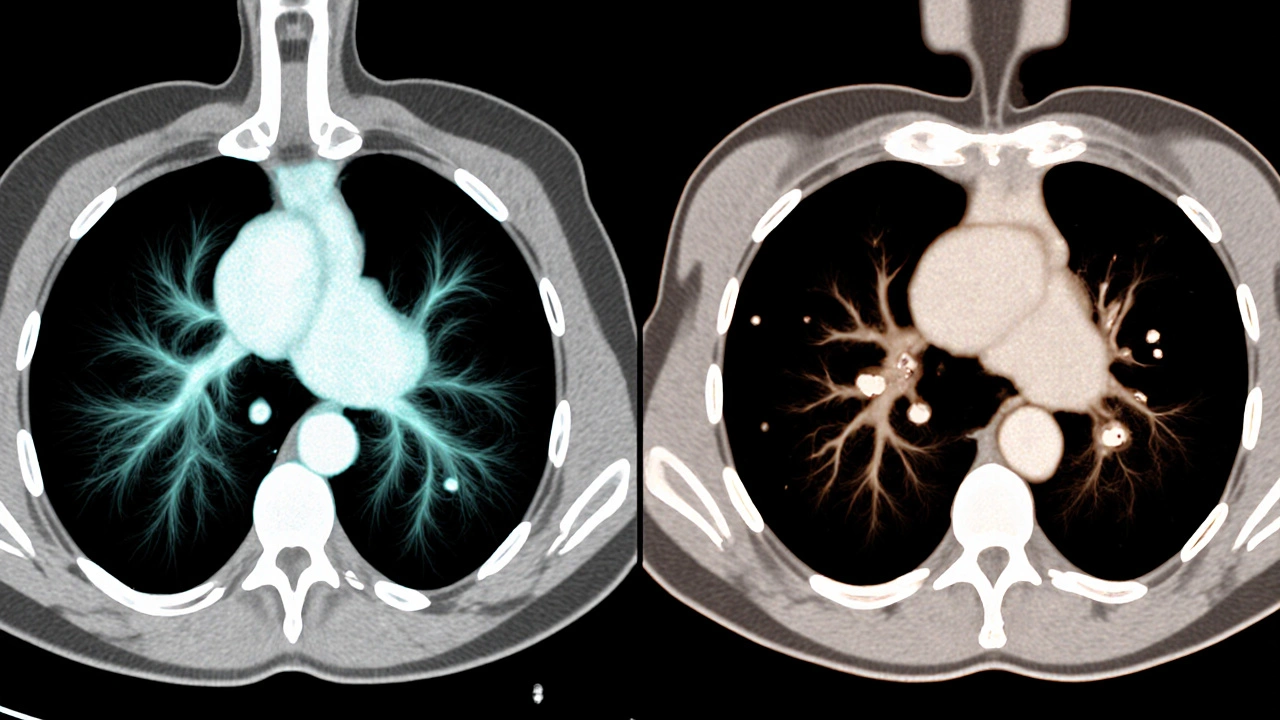

- CT vyšetření (počítačová tomografie) - umožňuje zobrazit jemné změny v plicní tkáni, jako jsou skvrny, zahuštění nebo noduly. U vapera se často objeví „ground‑glass“ opacities, které jsou méně časté u kuřáků.

CT nálezy | Ground‑glass opacities, subpleurální skvrny | Emfyzém, kalkulace, centrální skvrny |

Jak vidíte, rozdíly jsou subtilní, ale přítomnost charakteristických „ground‑glass“ oblastí a nízký podíl karcinogenních látek naznačují vaping spíše než konvenční kouření.

Standardní rentgenové snímky často neodhalí jemné změny spojené s vapingem. Pro detailnější nález jsou potřeba CT nebo HRCT (high‑resolution CT), které zobrazí „ground‑glass“ opacities a jiné subtilní struktury.